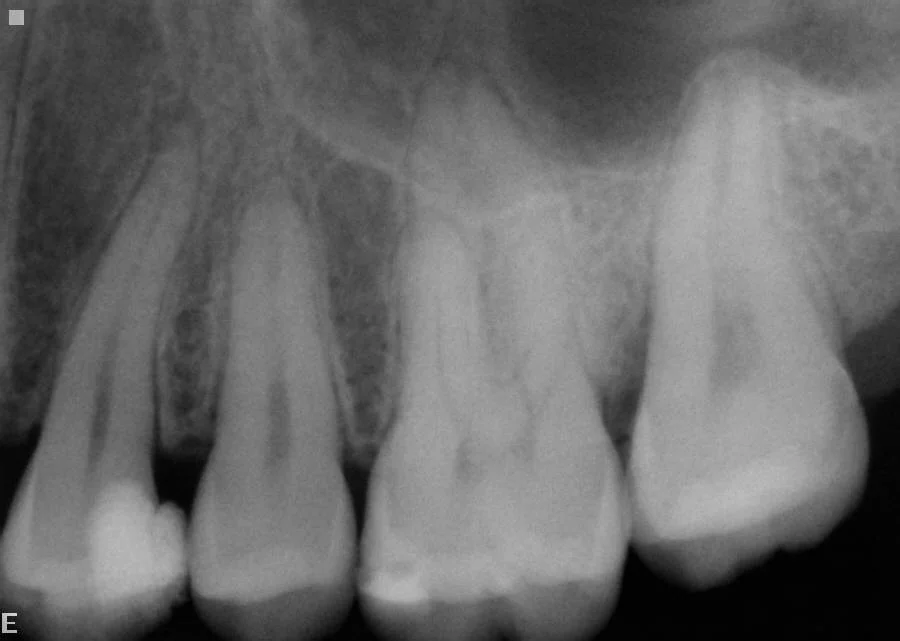

Before: Infected lower left teeth